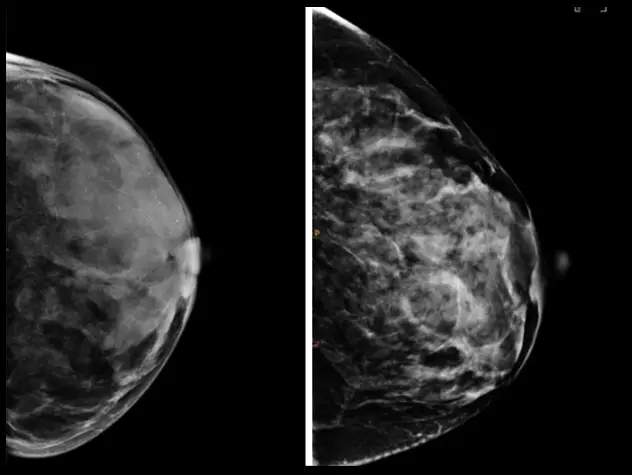

Through two world-class cancer centers – Columbia’s NCI-designated Herbert Irving Comprehensive Cancer Center and Weill Cornell Medicine’s Meyer Cancer Center, our team of physician-scientists are transforming care for cancer patients across a broad spectrum of malignant diseases and conditions. From pursuing novel laboratory research to better predict, diagnose and treat cancer, to conducting clinical trials of promising new therapies, our physicians provide personalized treatment plans to deliver optimal outcomes.